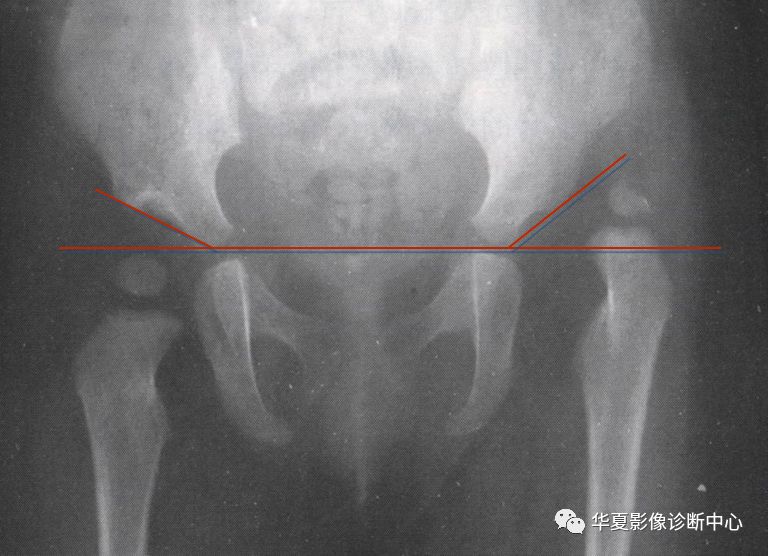

2.骨盆平片测量法

如图所示两侧髋臼Y形软骨连成为Hilg-eneriner线,简称为H线,股骨上端距H线之距离为上方间隙。股骨上端鸟嘴距坐骨支外缘为内侧间隙,正常均值上方间隙为9.5mm,内侧间隙为4.3mm。若上方间隙小于8.5mm,内侧间隙大于5.1mm应怀疑髋关节脱位。若上方间隙小于7.5mm,内侧间隙大于6.1mm可诊断为髋关节脱位,此法简易可靠。

3.Perkin象限

当股骨头骨骺核出现后可利用Perkin象限,即两侧髋臼中心连一直线称为H线,再从髋臼外缘向H线做一垂线(P),将髋关节划分为四个象限,正常股骨头骨骺位于内下象限内。若在外下象限为半脱位,在外上象限为全脱位。

新生儿正常股骨上端鸟嘴状突起位于内下象限内。若在外下象限为半脱位,在外上象限为全脱位。